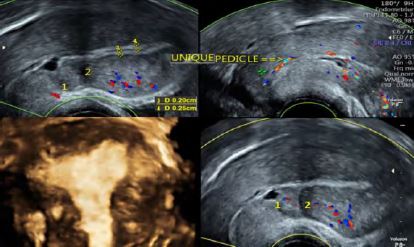

We report the case of a 57-year-old, gravida 6 para 6 patient, with a history of two caesarean sections, recurrent urinary infections and a recent asymptomatic COVID-19 incidentally discovered at systematic blood tests. The patient, menopaused at age 51, presented for post-menopausal uterine bleeding, with no additional symptoms or signs at physical examination. Transvaginal ultrasound revealed an anteverted anteflected adenomyotic uterus –in accordance with the recent diagnostic criteria for adenomyosis (3) – with two visualized uterine scars. The endometrial stripe was irregularly thick but remained within normal limits and did not exceed 4.5 mm of thickness. There was a thin layer of intra-cavitary fluid. At Doppler, a constant endocervical vascular pedicle was observed and aroused suspicion of an endocervical polyp (Fig 1).

Figure 1: Transvaginal Ultrasound. 1: distal isthmocele; 2 proximal uterine scar; 3,4: measurements of the irregularly thick endometrial stripe; Yellow arrow: single endocervical vascular pedicle; 3D coronal plane of the uterus: adenomyosis.